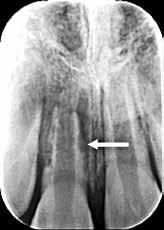

Fig. 11. A. Skematisk illustration af tand med pulpasten i pulpakammer og rodkanaler, hvilket kan gøre det vanskeligt at lokalisere kanalindgangene og udrense kanalerne (18). B. Bitewing-optagelse viser generaliseret dannelse af pulpasten i molarerne (pile). C. Periapikal optagelse af -6 med omfattende forkalkninger i pulpakammer og rodkanaler (pil).

Fig. 11. A. Schematic illustration showing tooth with pulp stone in the chamber and root canals creating potential difficulty in locating root canal orifices and instrumentation (18). B. Bitewing radiograph showing generalized pulp stone formation on molars (arrows). C. Periapical radiograph of mandibular left first molar with extensive calcifications in the pulp chamber and root canals (arrow).

Radiologiske fund

Forekomst af pulpasten i pulpakammeret kan blokere kanalindgangene, og der er derfor behov for forstørrelse for at kunne lokalisere kanalindgangene (Kategori B) (Fig. 11A-C). En kanal, der er meget snæver, kræver betydelige tekniske færdigheder under udrensning til korrekt rodmål (Kategori C).